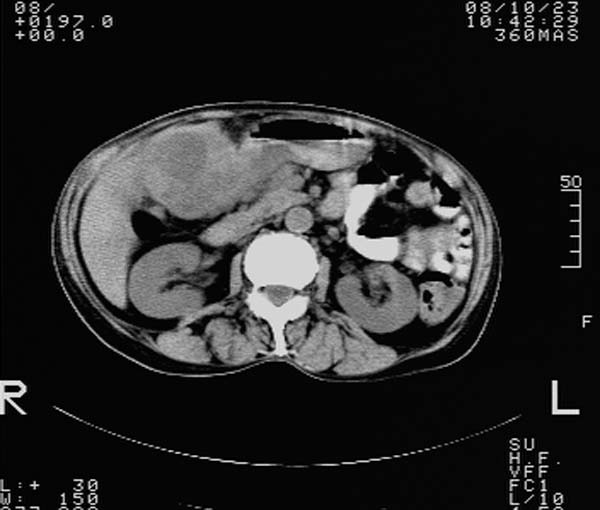

f,67y。反复右上腹痛。余无异常。

前五幅未服造影剂。后面图像有上传重复的。请战友们发表意见。

胆囊结石、胆囊癌伴邻近脏器受侵,不除外黄色肉芽肿性胆囊炎,建议增强扫描。肝多发囊性占位性病变,囊肿或囊性转移。

胆囊内结石,胆囊壁不规则增厚,胆囊胃窦区解剖结构欠清晰,楼主提示为少见病,考虑bouveret综合征?黄色肉芽肿性胆囊炎?肝内多发低密度占位,建议增强或b超

bouveret综合征(胆石性十二指肠幽门梗阻)应重点考虑。期待结果!

考虑bouveret综合征?黄色肉芽肿性胆囊炎?肝内多发低密度占位,囊肿?建议增强!